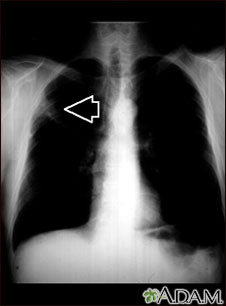

A chest x-ray is an x-ray of the chest, lungs, heart, large arteries, ribs, and diaphragm.

It may also be done if you have signs of tuberculosis, lung cancer, or other chest or lung diseases.

What Abnormal Results Mean

Abnormal results may be due to many things, including:

In the lungs:

- Lung tumor (noncancerous or cancerous)